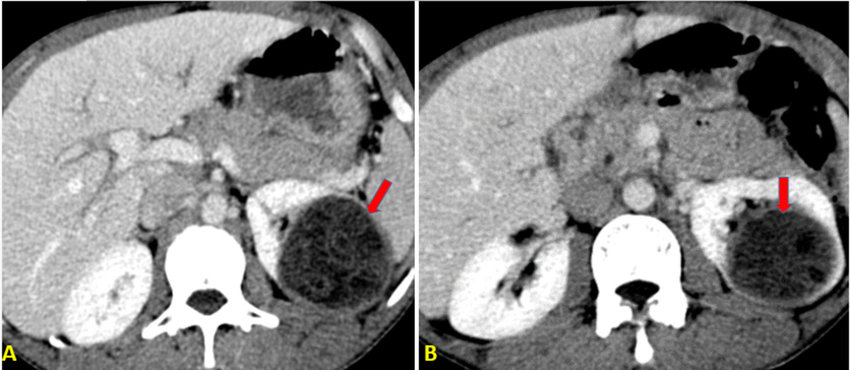

Cisti surrenalica

- Descrizione: Lesione cavitaria, spesso scoperta in modo incidentale, localizzata nella ghiandola surrenale e contenente materiale sieroso, emorragico o talvolta parassitario. Può rimanere asintomatica a lungo e sono spesso riscontri occasionali a ecografie, TC o RM eseguite per altri motivi.

- pseudocisti (le più frequenti), spesso post‑emorragiche o post‑traumatiche; hanno parete fibrosa, spesso con residui emorragici, calcificazioni e assenza di vero rivestimento epiteliale, espressione di un pregresso evento emorragico o necrotico della ghiandola.